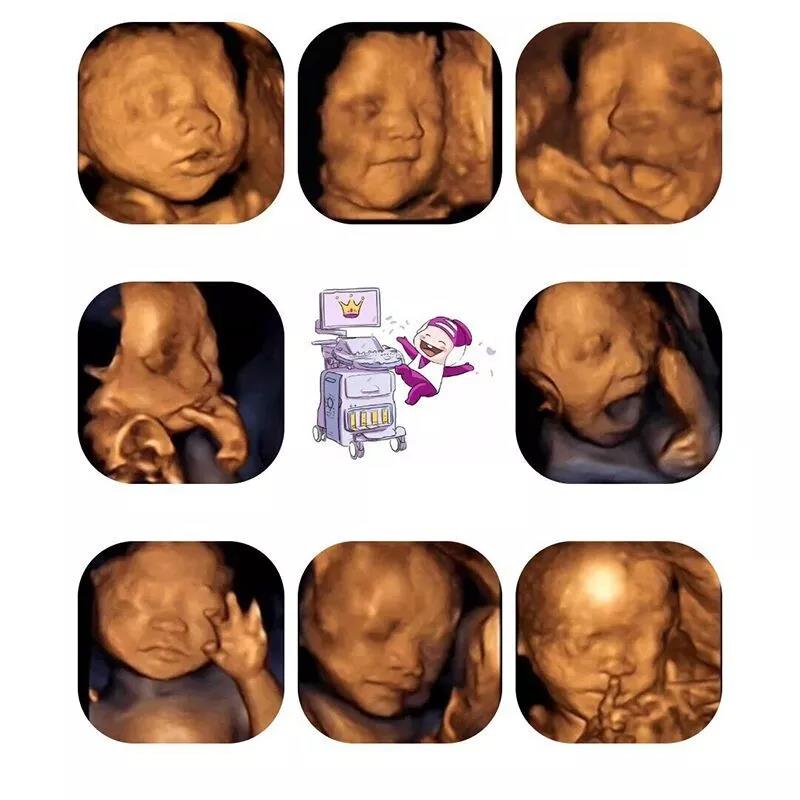

对于胎儿系统超声(四维彩超)这项检查,

这项检查可以观察宫内胎儿的生长发育情况,

胎儿系统超声(四维彩超)的影像更清晰,更准确

因为在这个时间段内,胎儿的结构已经基本形成,大小发育正适合,宫内羊水量储备充足,能保证胎儿在宫内有较大的活动空间;体表也比较丰满,胎儿骨骼回声影响比较小,这样就比较容易采集到清晰的图像,有利于医生进行胎儿畸形的筛查。

360度立体展示胎宝宝各项器官的发育情况